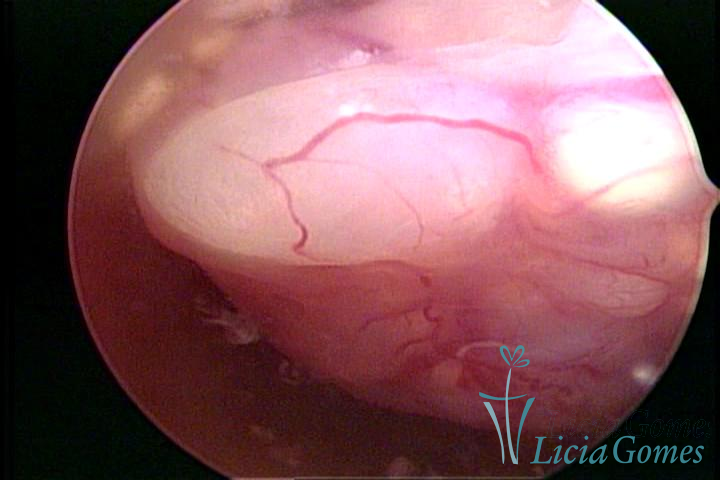

A histeroscopia permite analisar as características da superfície endometrial, não podendo avaliar a profundidade ou o grau de invasão miometrial.

Mas poderá verificar se as lesões são do tipo: focal; regional ou difusa

Este pode apresentar uma gama variável de aspectos macroscópicos, com aspecto pseudopolipoide; lembrando tecido cerebroide ou com reação deciduoide;a vascularização superficial é mais evidente e com vasos em formatos de saca-rolha ou espirais visualizando também a vascularização com atípias, com aumento do calibre dos vasos superficiais, pode ser encontrado também tecido em necrose, poderá haver um pequenos dendritos (papilomatoso).